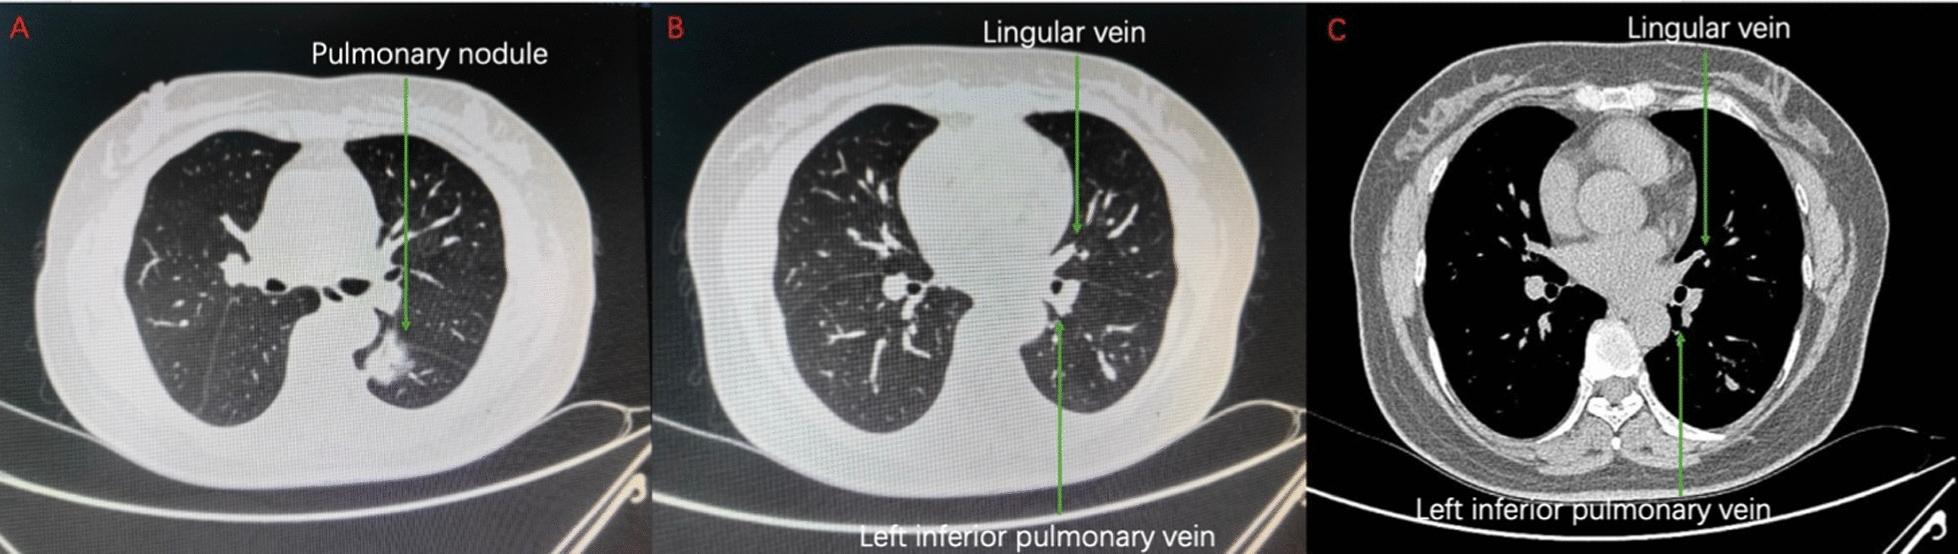

A 53-year-old female patient who underwent computed tomography (CT) examination due to chest discomfort, revealing the presence of a partial solid nodule highly suspected of early-stage lung cancer, measuring approximately 2.8 × 2.6 cm in the left lower lobe. Consequently, the patient underwent a single direction thoracoscopic left lower lobectomy and lymph node dissection. Intraoperatively, while attempting to dissect and free the left lower lobe vein from surrounding tissues, technical difficulties were encountered. Upon meticulous review of preoperative CT scans during surgery, an anomalous connection between the lingular vein of the left upper lobe and the left lower lobe vein was identified. Once this anatomical variation was confirmed, surgical intervention proceeded uneventfully without any significant complications.

Precise recognition of pulmonary anatomical structures before and during surgery is paramount in recognizing rare variations such as this one as it aids in preventing potential intraoperative injuries and minimizing postoperative complications.